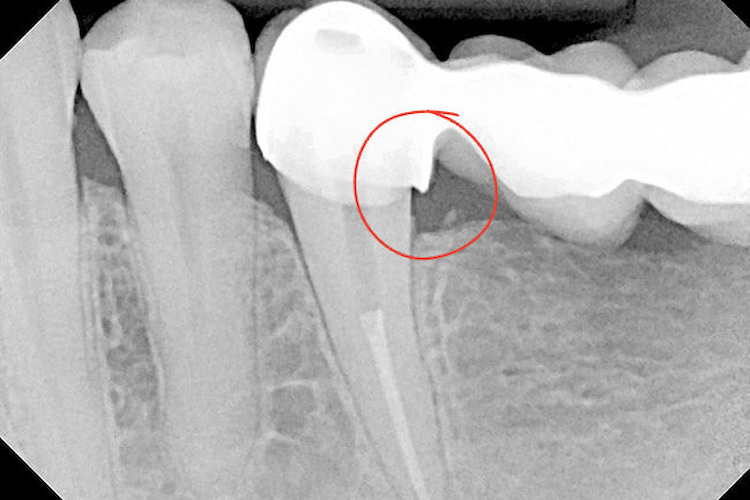

The dentist examines the crown using dental instruments and floss to check for irregular edges. They also observe how the gum tissue reacts during cleaning. X-rays provide a deeper view beneath the crown. They help identify:

- Hidden decay under the crown

- Bone loss or gum changes

- The exact position of the crown margin